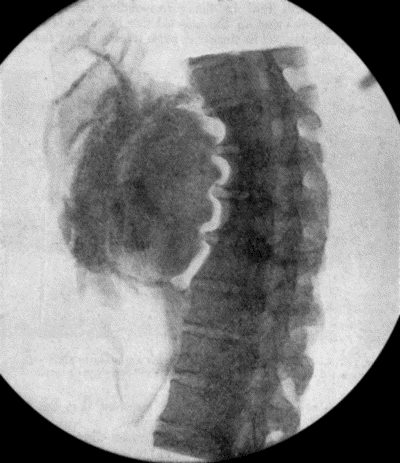

| 73. | Radiogram of Innominate Aneurysm after Treatment by Moore-Corradi method | 309 |

| 74. | Thoracic Aneurysm threatening to rupture | 313 |

| 75. | Innominate Aneurysm in a woman | 315 |